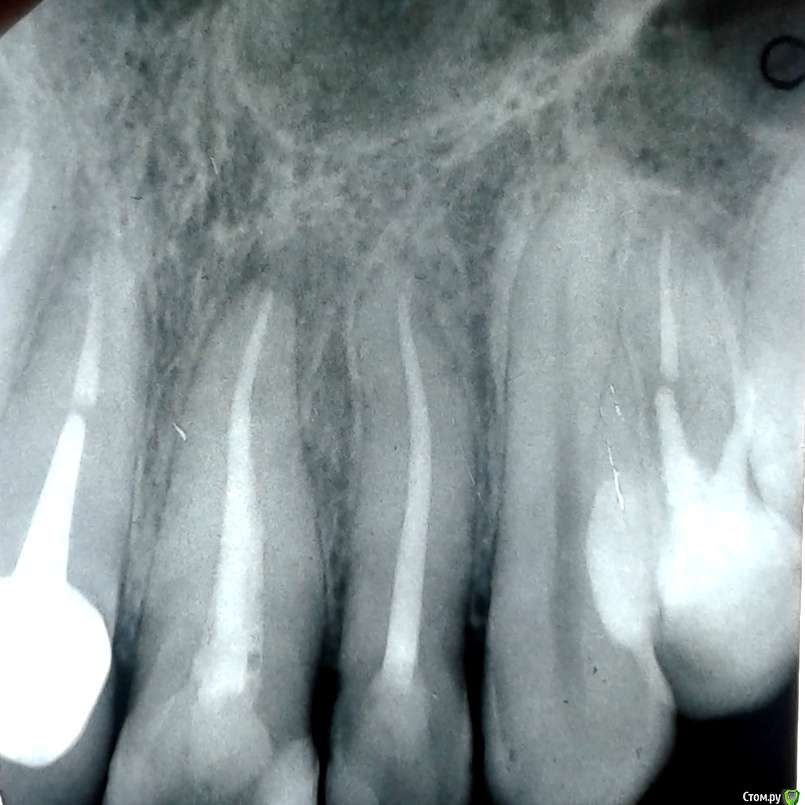

Евгения Григорьева Опубликовано 29 апреля, 2019 Поделиться Опубликовано 29 апреля, 2019 Киста на первом зубе рядом с коронкой (и возможно на втором?) Не беспокоила вообще, в конце марта возникла острая боль именно в нем. Снимок сделан до начала лечения. По обращении врач прочистил канал, поставил метапекс на неделю под временную (розовую) пломбу. От метапекса зуб ныл (м.б. аллергия, но это неважно). После этого проверил сиреневым штифтом (не знаю, как называется) нет ли воспаления - его не было. Поставил коласепт на две недели, тоже под розовую пломбу. После этого опять проверил сиреневым штифтом - он обесцветился (врач сказал "значит есть воспаление") и опять поставил коласепт под розовую пломбу, теперь на три недели. Нормально ли по времени такое длительное лечение воспаления, да еще и под розовой пломбой? Оба раза после коласепта ощущение сладковатого геля во рту между первым и вторым зубом (но не на месте пломбы). Это протечка или эффект от вмешательства? Целесообразно ли найти клинику с депофорезом? Нужно ли лечить второй и нужно ли делать это сейчас, одновременно с первым? Ссылка на комментарий